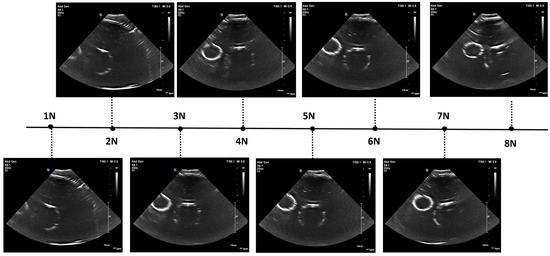

The image acquisition test followed a similar protocol to the standalone force-control experiments, so we used the same data analysis method to evaluate the force during the scan, as shown in the upper graph of Figure 21. In this experiment, 57.0% of the applied forces fall within the 3–6 N range, while 98% of forces remain within a ±2 N range (1–8 N). The standard deviation of the force readings is 1.59 N, which is lower compared to readings without the fat layer and ultrasound gel.

Figure 21.

Force values and distributions in automated ultrasound image acquisition experiment on phantom with adipose layer. The top subfigure shows force variation over time, with 3 N and 6 N thresholds marked; the middle subfigure depicts the force value distribution, highlighting ranges below 3 N, 3–6 N, and above 6 N; and the bottom subfigure displays the time proportion within each force range. Red, green and blue colours in the middle and buttom graphs match with each other.

Figure 22 displays the ultrasound images acquired by the robot during the automatic sweep under varying force levels. Overall, the robot successfully generated clear abdominal aorta ultrasound images without human intervention. In these images, vessel walls appear as bright circular shapes, with water inside the circle and the surrounding area comprised of the phantom material (polyurethane). The smaller vein consistently appears clearer than the larger aorta, likely because it is closer to the phantom surface and, therefore, undergoes less attenuation.

Figure 22.

Ultrasound images acquired by robot at varying force levels on AAA phantom.

We recorded the applied force for each ultrasound image and observed that the clearest images were obtained at force levels of 5 N and 6 N, while forces outside this range resulted in reduced image quality. The decline in quality at higher forces may be due to deformation of the phantom, impairing contact between the probe and the surface or compressing the embedded vessels—an issue unlikely to occur in real participants. In human subjects, signal strength and image clarity typically improve with increased force as the distance to the area of interest decreases and attenuation is reduced. However, excessive force can introduce artefacts and discomfort. To better understand this force–image relationship, we propose measuring the distance to the centre of the abdominal aorta (derived from the ultrasound depth scale) as a metric correlated with probe force and image quality in future human trials. These preliminary phantom tests demonstrate the robot’s ability to autonomously acquire high-quality abdominal aorta images, laying a foundation for further studies to optimize the balance between image quality, patient comfort, and operator considerations in clinical settings.